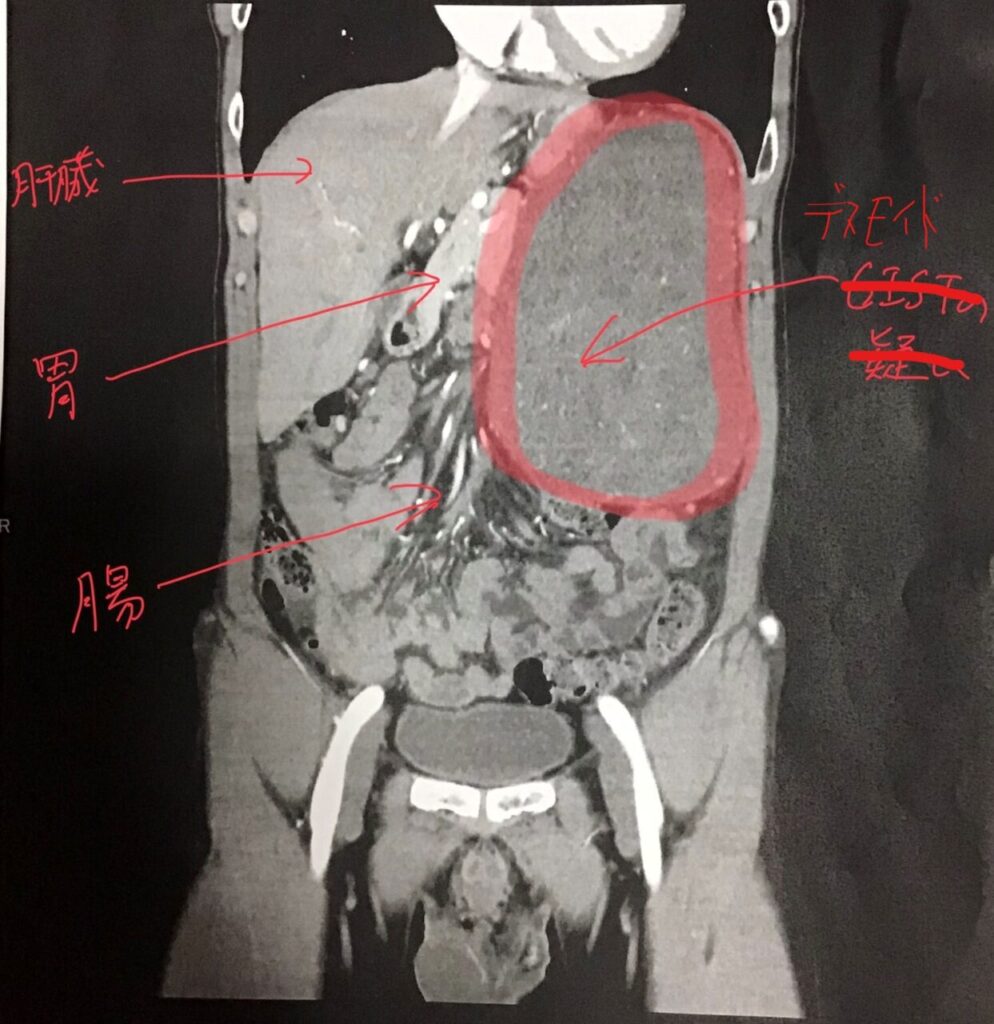

| 診断 | 触診で肋骨の下に固い感触があったためエコーで検査したところ、15cm級の腫瘤があるとのこと。肝臓や腎臓からは分離して見えるらしい(境界がはっきりしているので浸潤はなく良性腫瘍と思いたい)。大病院で診てもらったほうが良いとのことで、地元で大きな病院へ紹介してもらった。 大病院での診断ではすぐに摘出したほうが良いとのことで、コロナ禍かつゴールデンウィーク前のややこしい時期であったが手術をねじ込んでくれた。 なお、病理検査前の診断は「GISTの疑い」であった。 | 脳神経外科でめまいに関する検査を受けたが特に異常は無し。念のため頭部MRIを撮っておこうとなり、予約して後日検査したところ脳に直径22mmの腫瘍があることが発覚(ただし、めまい症状とは関係ないとのこと)。1か月後に再度造影剤ありのMRIを撮り、拡大がないことから悪性度は低いとの見立て。言語中枢に近いところに腫瘍があるため除去には覚醒下手術が必要で、この手術ができる大学病院を紹介してもらった。 さすがにヤバそうな病気のためセカンドオピニオンを受けたが同様の診断であった。 当初紹介された大学病院で診てもらい、摘出手術を受けることになった。 【備忘録】グリオーマ・びまん性星細胞腫:脳腫瘍が発覚した経緯2 |

| 手術中 | 9:00~昼過ぎまでかかったと思う。 心電図や点滴や硬膜外麻酔などの準備以降は全身麻酔で記憶なし。 腫瘍のサイズが大きいため胸元からへその下まで縦に大きく切って、へその上から横にも切った。 腫瘍が胃や膵臓や大腸に癒着と浸潤があり、胃は剥がした、膵臓は削った、大腸は5cmを切断してつないだ。 | 9:00~16:30までかかった。 心電図や点滴や硬膜外麻酔などの準備から開頭までは全身麻酔で記憶なし。腫瘍の取り出し以降は意識あり。 脳内のナビゲーションシステムとか凄そうなマシーンを使って、手術室にはたくさんの人が付いてくれていた。主治医と助手の脳神経外科医、麻酔科医師、手術室看護師、言語聴覚士、理学療法士、臨床検査技師。医学生たちの見学もあり。 腫瘍を取りだす際は目の前の画面に映されたモノの名前をずっと声に出してしゃべる。その間に電気刺激を与えて除去部分を探る。電極が言語中枢に触れると全く言葉が出なくなるので、ちょっとでも言葉に詰まると言語療法士がストップをかけるというやり方。 【備忘録】グリオーマ・びまん性星細胞腫:入院6日目(手術当日) |